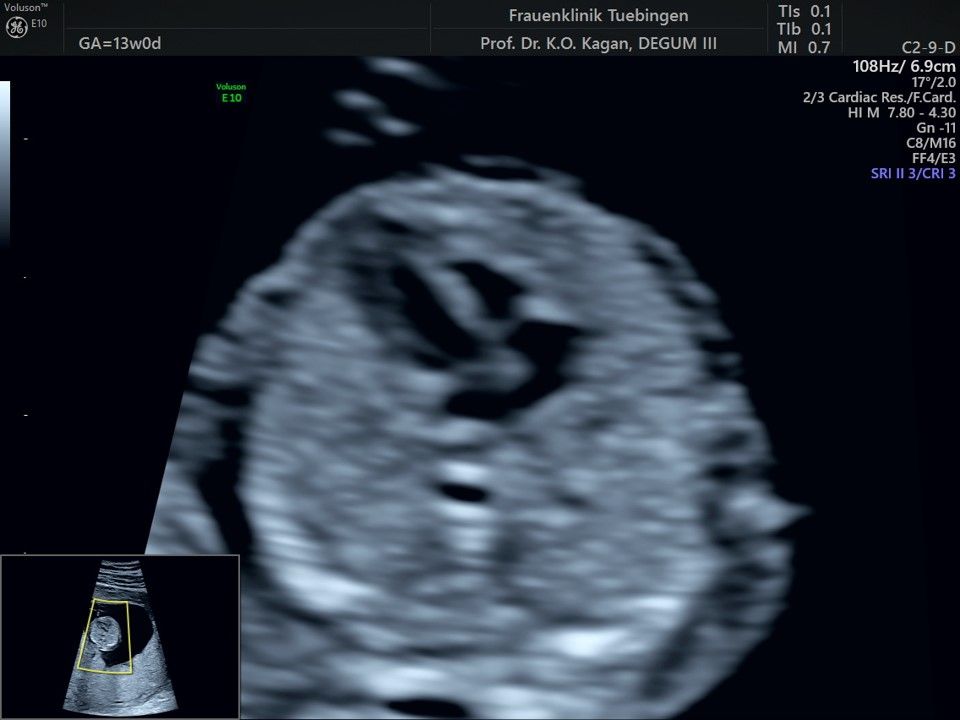

Im Rahmen des Ersttrimester-Screenings untersuchen wir die Organe des Feten mittels Ultraschall. Dabei machen wir auch gerne ein Bild für Sie.

Obwohl der Fet zu diesem Zeitpunkt erst zwischen 5 und 8cm groß ist, lassen sich bereits etwa die Hälfte aller schwerwiegenden Fehlbildungen erkennen bzw. ausschließen. Sollten wir eine Auffälligkeit sehen, werden wir mit Ihnen den Befund und das weitere Vorgehen ausführlich besprechen.

Die eigentliche Organuntersuchung findet um die 20.SSW (zweites Screening) statt. Das Ersttrimester-Screening und das zweite Screening sind sich ergänzende Untersuchungen und ersetzen sich gegenseitig nicht.

Herz